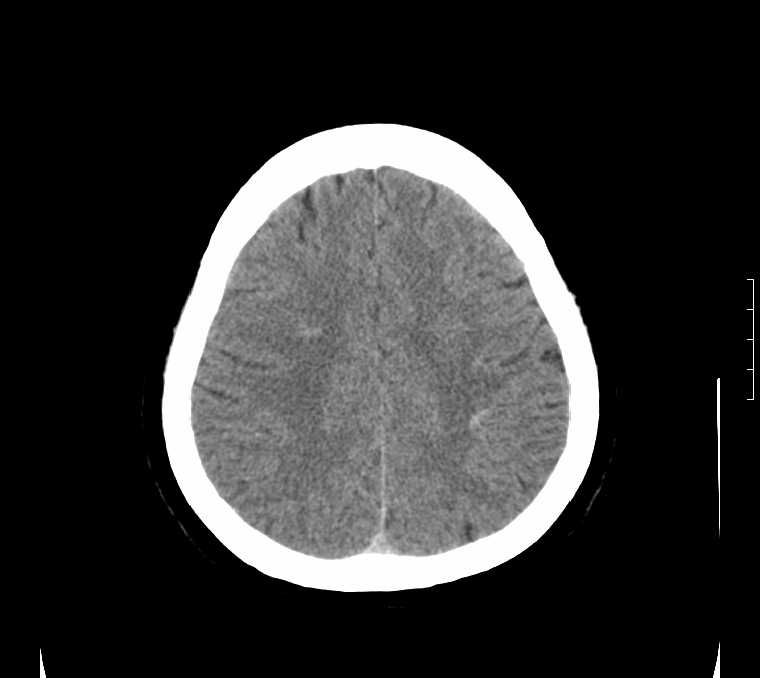

标题: CT24387:看看这例脑部改变!!

老年女性。头晕。

鉴别于特发性家族性脑血管亚铁钙沉着症(fahr`s病)与甲状旁腺机能低下之间,请结合临床及相关实验室检查。